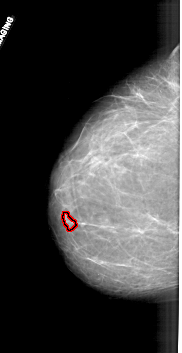

FILE: A_1711_1.LEFT_MLO.OVERLAY

TOTAL_ABNORMALITIES 1

ABNORMALITY 1

LESION_TYPE MASS SHAPE LOBULATED MARGINS CIRCUMSCRIBED

ASSESSMENT 4

SUBTLETY 3

PATHOLOGY BENIGN

TOTAL_OUTLINES 1

BOUNDARY

LEFT_MLO LINES 6736 PIXELS_PER_LINE 2956 BITS_PER_PIXEL 12 RESOLUTION 43.5 OVERLAY